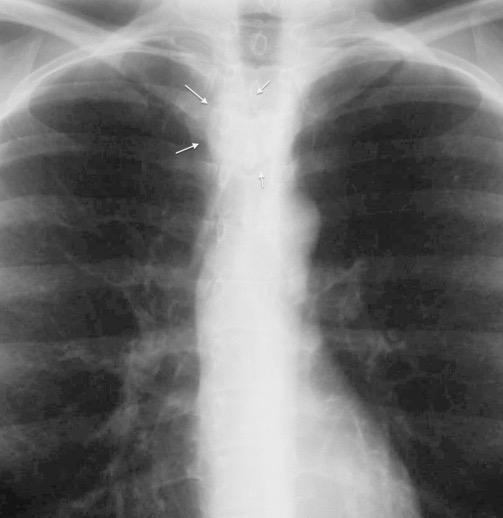

Triada de Garland

Ganglios paratraqueales derechos e hiliares bilaterales

95% de pacientes tienen ganglios hiliares bilaterales aislados o con afectación mediastínica (espec. paratraqueal derecho).

Criado E et al. Pulmonary sarcoidosis: typical and atypical manifestations at high-resolution CT with pathologic correlation. Radiographics. 2010